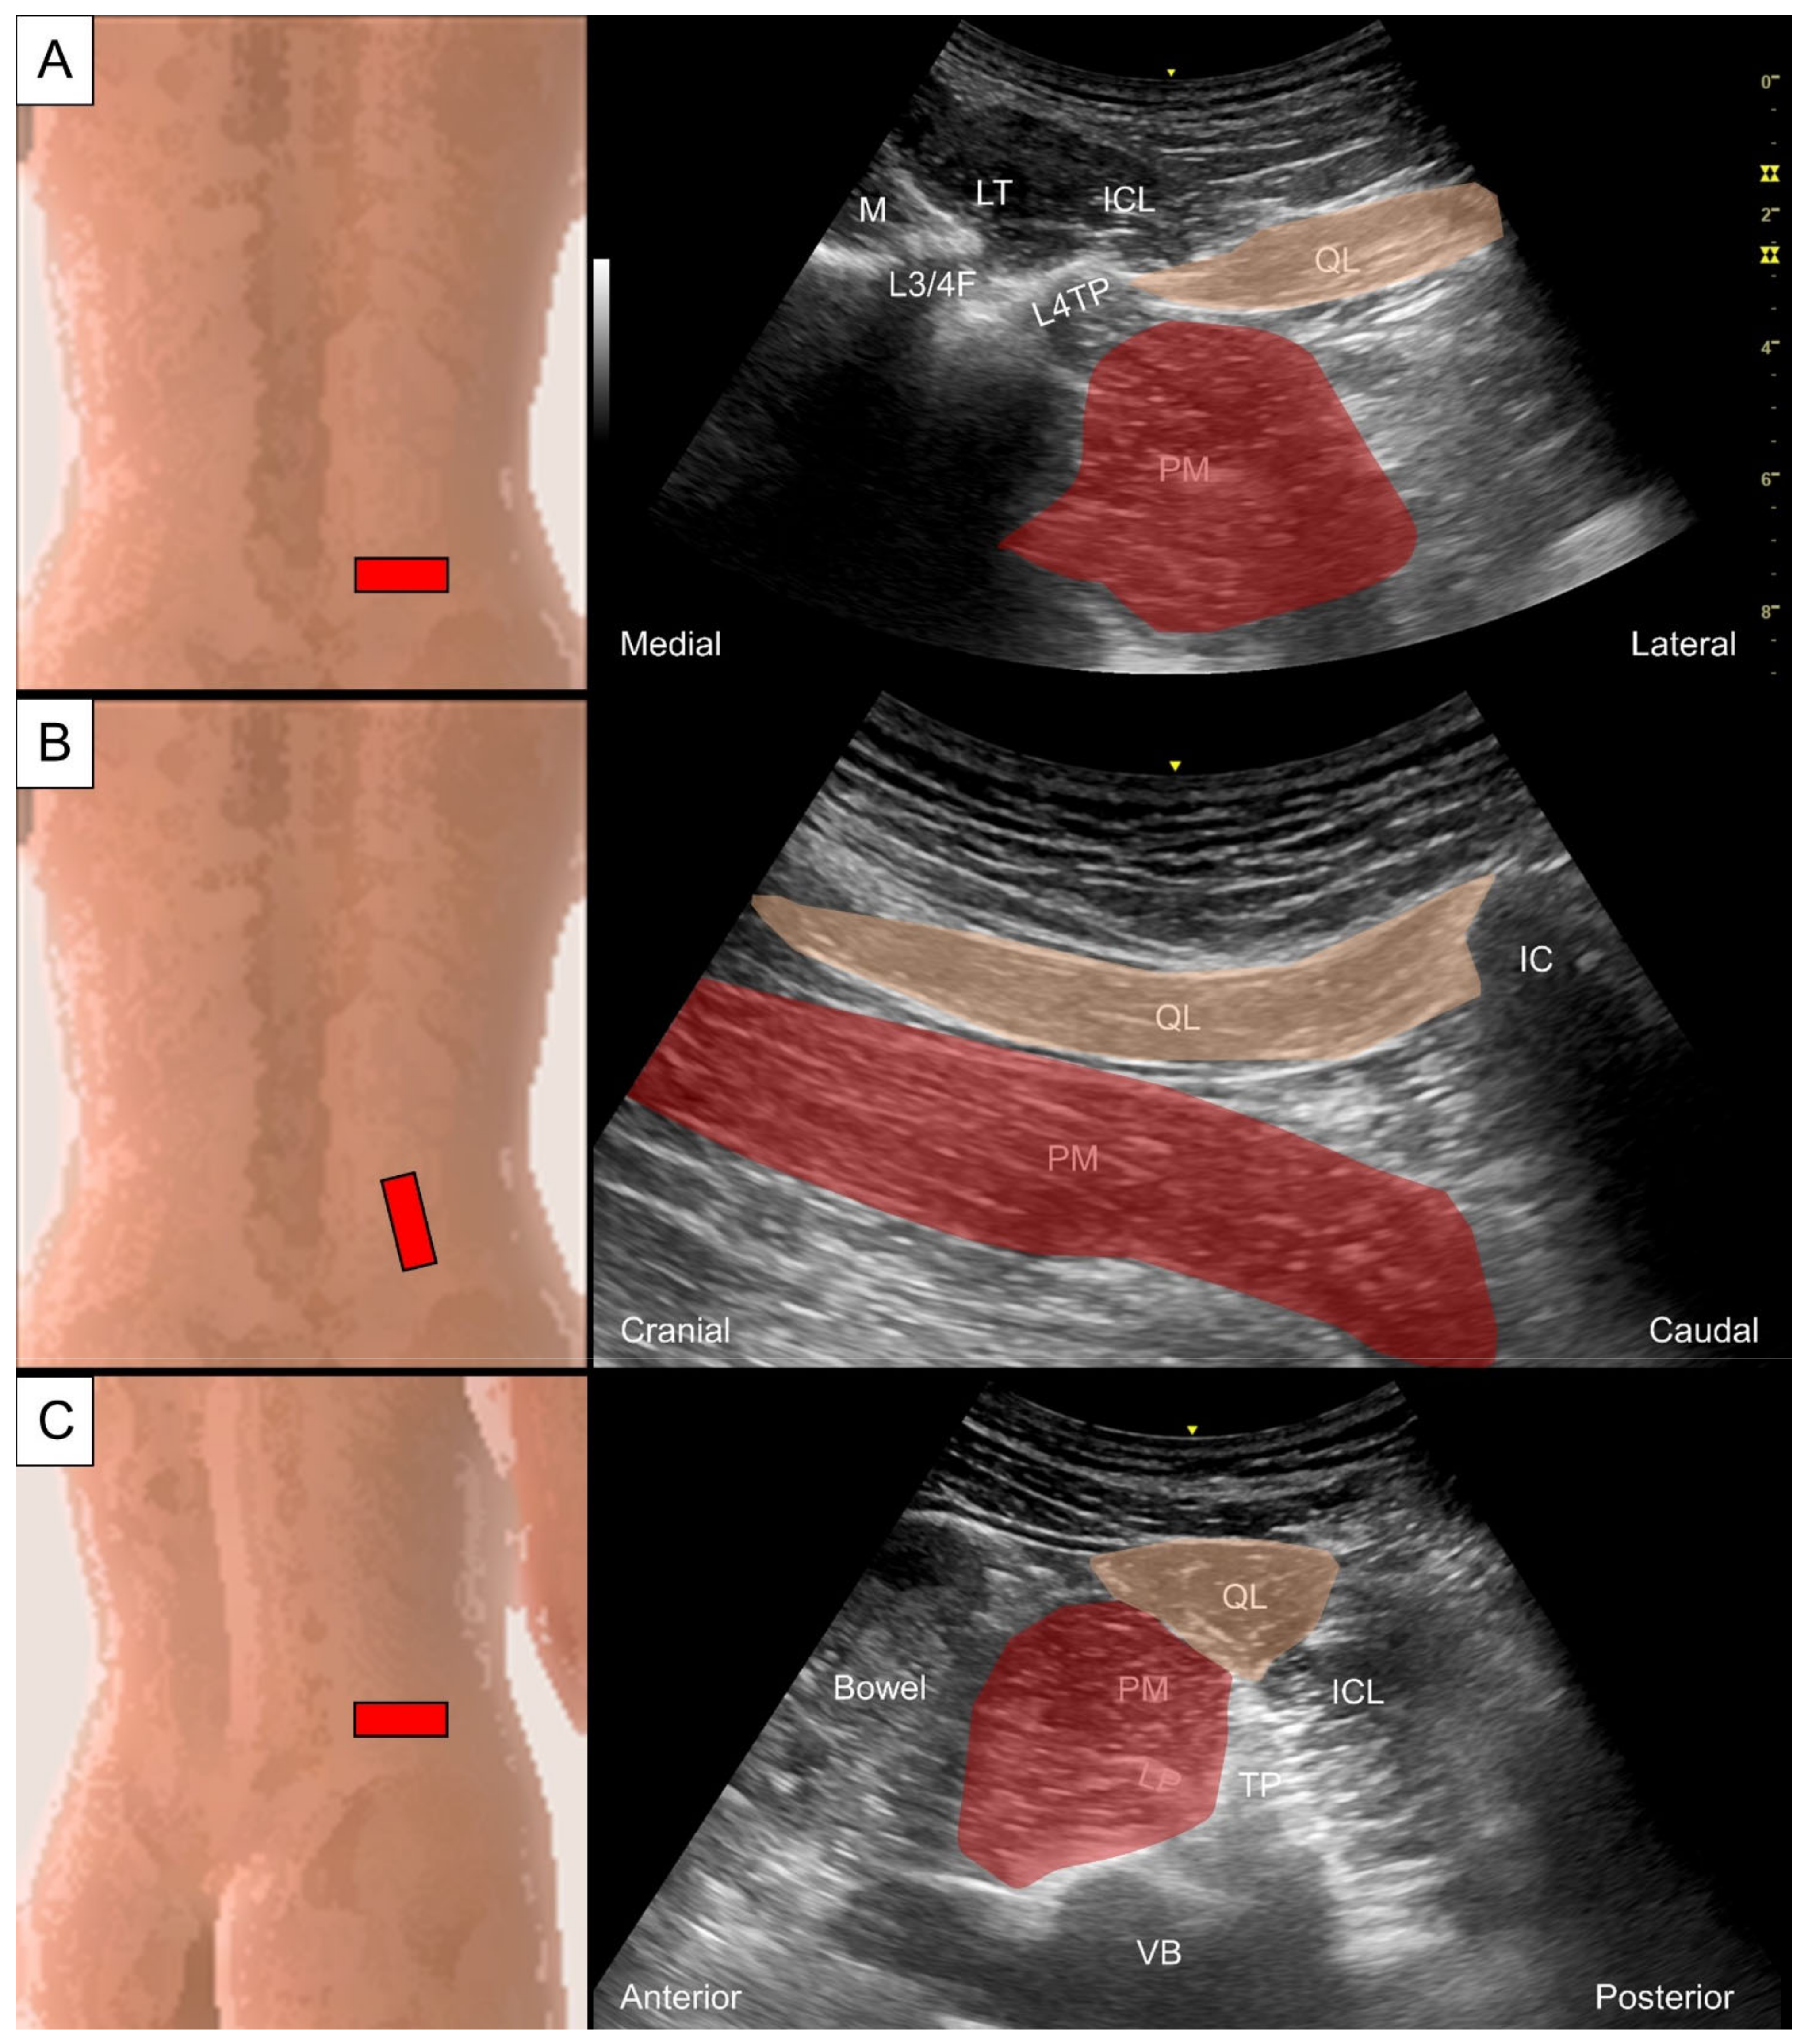

6.3. Quadratus Lumborum and Psoas Major

6.3.1. Anatomy

6.3.2. Sonographic Scanning

6.3.3. Clinical Relevance